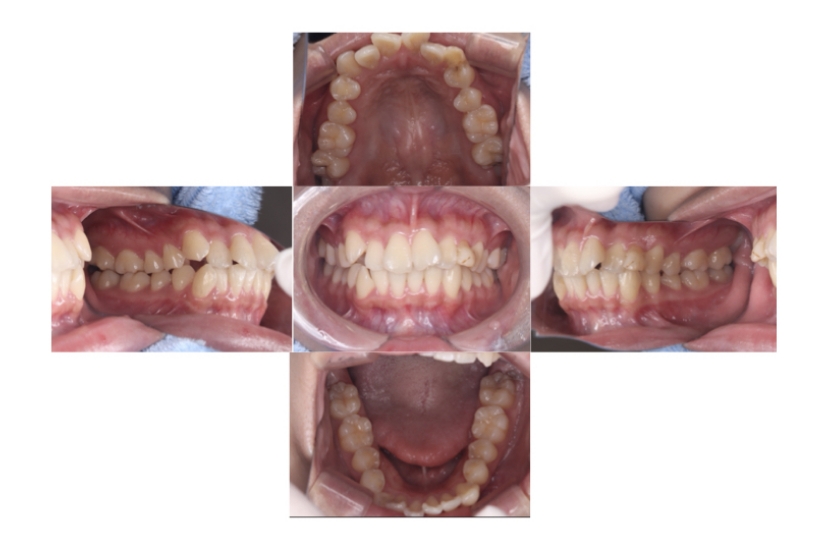

症例3

叢生

抜歯

ブラケット矯正

上下顎叢生(上下の前歯のガタガタ)のケースです。

装置はラビアル(上下表側)で、上下顎の小臼歯を4本抜歯を行っています。抜歯したスペースを使って、上下の前歯の後方移動と叢生(ガタガタ)の改善を行っています。

主訴 八重歯を治したい。

年齢・性別 25歳 女性

お住まいの地域 神奈川県川崎市

治療方針 抜歯スペースを利用して上前歯の叢生(ガタガタ)の改善

抜歯部位 上下顎左右第一小臼歯

使用装置 ラビアル(上下表側)、顎間ゴム

治療期間 1年11か月

治療回数 16回

リテーナー クリアリテーナー

BEFORE

AFTER